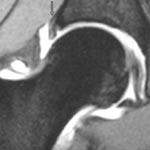

Degenerativ labrum viste økt signalintensitet i labrum uten affeksjon av overflaten med inntakt recess hos to pasienter (fig 3) og med manglende fremstilling av recess hos tre pasienter (fig 4). Sistnevnte ansees forårsaket av labrumhypertrofi. Labrumruptur ble diagnosisert hos ti pasienter. Ruptur ble beskrevet når man kunne identifisere kontrast mellom labrum og acetabulum (fig 5) eller imbibering av kontrast i labrum (fig 6). Alle rupturene satt i øvre del av labrum.To av disse pasientene er operert, og vårt funn ble verifisert. Begge var aktive fotballspillere, og de hadde henholdvis stadium 2B og stadium 3B ved MR-artrografi. Dette samsvarte med de artroskopiske funn. Den tredje pasienten som er operert, viste forandringer forenlig med villonodulær synovitt. Også dette ble verifisert ved artroskopi (fig 7).

Etter at det er tatt konvensjonelle røntgenbilder av det aktuelle hofteleddet, blir pasienten lagt på ryggen på et gjennomlysningsbord. En assistent står ved fotenden og trekker i ekstremiteten samtidig som den blir rotert innover. Dette frembyr en liten utposning av leddkapselen medialt ved collum femoris som vil være lett tilgjengelig for punksjon. Under sterile forhold rettes en 20 gg nål ved hjelp av gjennomlysning mot dette området. Man stikker lateralt for a. femoralis. Det settes forsiktig 1 % Xylocain. Hvis man ikke kjenner noen motstand under instillasjonen, er nålen sannsynlig plassert intraartikulært. For å verifisere dette settes det forsiktig ikke-ionisk kontrastmiddel (fig 1). Dersom kontrastmidlet legger seg rundt collum og caput femoris, settes det fortynnet gadolinium (fortynnet til 0,2 mmol/l). I alt settes det 6 – 8 ml væske. Pasienten får beskjed om å bevege hoften. Et røntgenbilde tas for å verifisere at nålen er kommet intraartikulært og for å se etter eventuelle større patologiske forandringer, som avansert synovitt eller større frie legemer.